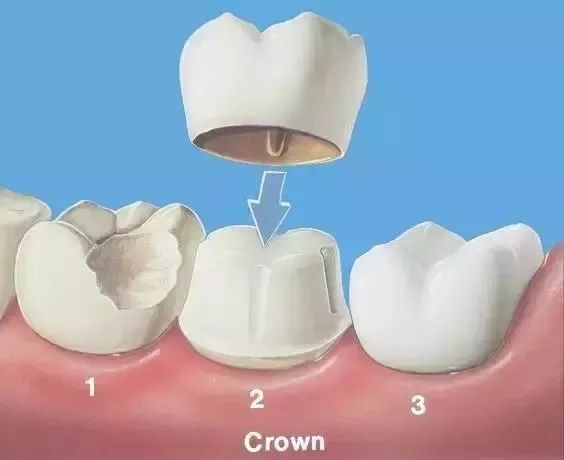

最后给牙齿做一个全瓷/烤瓷牙冠,起到保护作用,同时也解决了牙齿颜色灰暗的问题,更加美观。

做完根管治疗后的牙齿

Q2:根管治疗后非要做牙冠吗?

根管治疗后的牙齿,失去了来自牙髓的营养供应,就像失去树根的树木一样,

慢慢枯萎变得脆弱、颜色灰暗,也更容易发生劈裂。

因此,为了保护脆弱的牙齿,牙医们就会在做完根管治疗后,

通常会需要再给牙齿做一个牙冠,扛起咀嚼的重担。

另外,除了根管治疗本身的费用外,还需要加上手术后保护牙齿的牙冠费用,

而牙冠的价格,主要与材料有关。